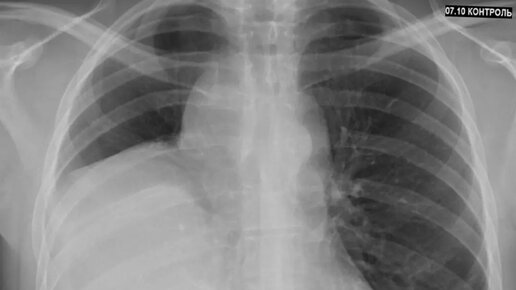

Мы привыкли, что любое упоминание о злокачественном процессе в грудной клетке ассоциируется у нас исключительно с раком - опухоли из эпителия бронхов/бронхиол. Редко, но бывают исключения. Как например, у этого молодого человека 36 лет - более чем за полгода до госпитализации по поводу ОРВИ была выполнена ФЛГ - в правом лёгочном поле найдено обширное затемнение (образование? гидроторакс?). До момента проведения ФЛГ пациента ничего особенно не беспокоило - периодический сухой кашель и неприятные ощущения в грудной клетке...